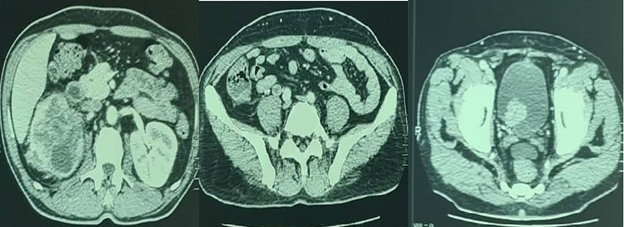

An abdominal ultrasound showed moderate dilation of the right pyelocaliceal cavities with echogenic tissue content. The right ureter is dilated ending in the bladder by a heterogeneous vegetative mass of 3 cm. A CT scan of the thoracic, abdominal and pelvic regions showed hydronephrosis of the right kidney as well as a tumor of the right upper excretory system (pyelon, pyelo-ureteral junction and iliac ureter) and the bladder. Multiple metastasis in the lung, spleen and liver as well as multiple metastatic lumbo-aortic lymph nodes were also noted (Figure 1).

Figure 1 CT scan showing bladder and iliac ureter tumor with dilation of the pyelo-calicial and ureteral cavities.